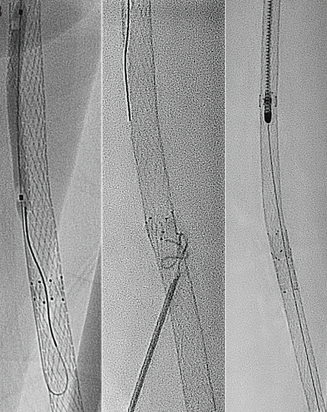

The device consists of a long spiral inside of the catheter that rotates at up to 40-60,000 revolutions per minute, depending on the device size, and in doing so, creates a very powerful suction force. The head of the device is beveled at the tip and spins as well, detaching the material from the arterial wall and fragmenting it into small pieces that are then transported out of the artery through two openings within the catheter tip. The observation of the stent walls moving towards the catheter tip during activation demonstrates how powerful the aspiration force of the catheter is. Occasionally, the Rotarex™ Atherectomy Device may stop automatically in these scenarios due to a safety mechanism engineered into the device when too much resistance occurs. A second safety mechanism is a return button that if pressed, spins the spiral in the opposite direction for a very short time, releasing any material blocking the catheter tip/spiral. Over the past 15 years that we have used the Rotarex™ Atherectomy Device, we have never experienced the catheter becoming hooked in a stent, making retrieval of the catheter impossible, an event which can, for example, occur when using a directional atherectomy system within a stent. The Rotarex™ Atherectomy Device has been shown safe to use inside a stent at our institution.

Certainly, femoropopliteal in-stent occlusion cases can be encountered, in which thrombotic material seems to remain adjacent to the stent after the treatment with the Rotarex™ Atherectomy Device. We use thrombolysis for a few hours if the remaining thrombus is very apparent, or we continue with balloon treatment and repeat the Rotarex™ Atherectomy Device treatment if the thrombus is dislodged from the arterial wall after ballooning, being either still adjacent to the stent or having embolized.

There are, of course, several tips and tricks to learn for an optimal performance of the Rotarex™ Atherectomy Device. The learning curve is, however, not too long. I would start with rather acute or subacute in-stent reocclusions of the femoropopliteal segment. As mentioned, we prefer an 8 French device cross-over approach in this type of lesion. We prefer relatively stiff, braided sheaths. Advancement of the device through the lesion is slow, and movements are back and forth. Have an eye on the filling of the bag, which is attached by a tube to the device and should hang down from the operating table. It may occur that the thrombotic material is very organized, occluding the spiral and catheter at some point. Occasionally, a second interventionalist should press on the tube connecting the device to the debris bag while the first operator continues to activate the device. This allows for an easy check as to whether blood and debris is being transported out of the artery into the bag. If no filling of the tube during pressing can be observed, the catheter should be taken out and saline should be aspirated to flush the catheter. If there is no filling of the bag during activation within the artery but the stent struts are pulled towards the Rotarex™ Atherectomy Device tip, the reason is probably a hyperplastic stenosis at the origin of the stent that is not allowing any blood flow to follow into the occluded stent during the Rotarex™ Atherectomy Device passage. Predilatation of the stent entrance can solve this problem before resuming with the Rotarex™ Atherectomy Device treatment.